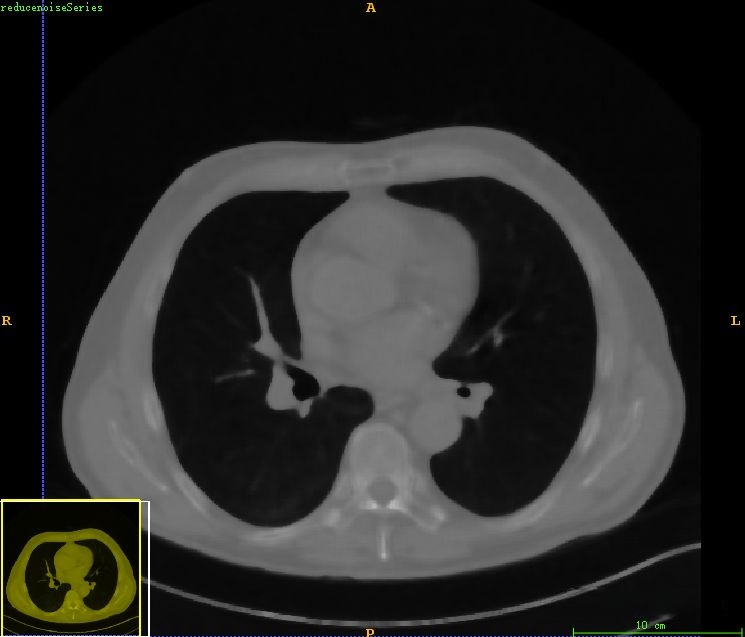

在本案例中,我们可以直接调用挑战赛提供的Mask来省略这一步骤的处理。而在本案例中,则对之前的医学图像处理案例(一)——基于CT图像的肺分割进行了深入分析与拓展研究,在这一过程中主要包含了六项关键步骤:首先,在观察图像时会发现存在一定的噪声干扰,并通过应用中值滤波器来去除这些噪声影响;其次,在进行图像分割时采用了大津阈值法作为主要手段;第三步则是对背景目标进行识别并予以剔除;第四步则重点进行了对噪声信息的尽量去除;第五步是对肺部轮廓边缘进行重构;第六步则最终实现了肺部组织区域的提取与确定。

在原始CT图像上观察到存在明显的噪声干扰,在后续的肺部分割过程中可能会受到一定影响为此处采用了中值滤波方法来进行预处理经过中值滤波处理后图像中的噪声得到了有效的抑制值得注意的是在此过程中血管信息也会被一定程度地抑制但这并不影响整体效果这一预处理步骤的主要目的是为了获得较为完整的肺部区域信息

最后得到肺部区域图像如下所示。